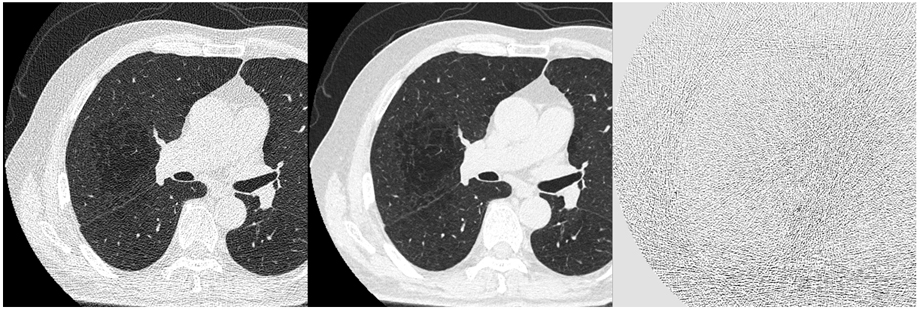

検査ワークフローにおいては、各工程においてAI技術*3を活用して開発した自動化ソリューションやSYNAPSE VINCENT Core*4との連携による効率化を提案してきた。今回、さらに検査オーダー、検査後の後処理においてAI技術を活用して開発したワークフロー向上技術を強化することで、検査プロセス全体を通じた効率化を目指す。画像処理においてはDeep Learningを活用して開発した画像ノイズ低減処理技術DLR Focus*2,3を新たに搭載し、さらなる低被ばく化をめざした。

(3)DLR Focus*3(Deep Learningを活用して開発した画像ノイズ低減処理技術)

従来の逐次近似処理では、処理後の画像ボケやコントラスト低下などを理由に、撮影線量を十分に下げられないなどの課題があった。そこで、さらなる低被ばく化をめざして、Deep Learningを設計段階で用いて画像再構成技術DLR Focusを開発した。DLR Focusは、低線量撮影したノイズの多い画像に対して、構造を維持したままノイズを低減する*8。

*8 AAPM CT Performance Phantomを用いて、最も強いDLR強度を使用して試験し、ノイズ低減処理前後の差分画像に対するファントム内構造部のプロファイルの標準偏差を、ボケやすさを表す指標として用いて評価した場合。